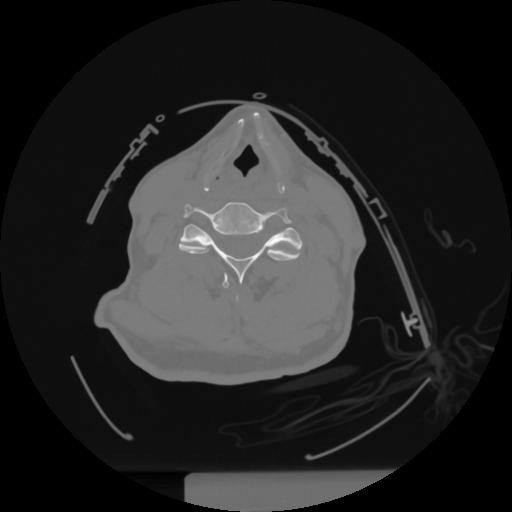

12 P.BLANDAS,,Vol,0.5,P.BLANDAS,,